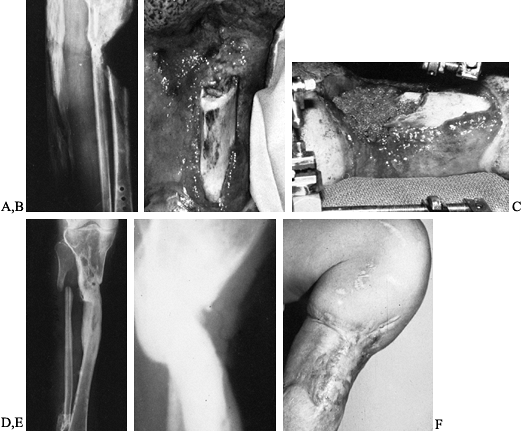

![]() |

Figure 133.16. A: Anteroposterior radiograph of the distal tibia and fibula showing a comminuted fracture of the tibia and plafond. B,C:

Anteroposterior and lateral films taken following open reduction and internal fixation show fractures nonunited at the time of infection. D: Anterior photograph of the ankle shows exposed metal and ankle joint with a necrotic anterior tibialis tendon after an acute postoperative infection. E: There is no evidence of infection 9 months following removal of metal and a free-vascularized latissimus dorsi muscle transfer. |